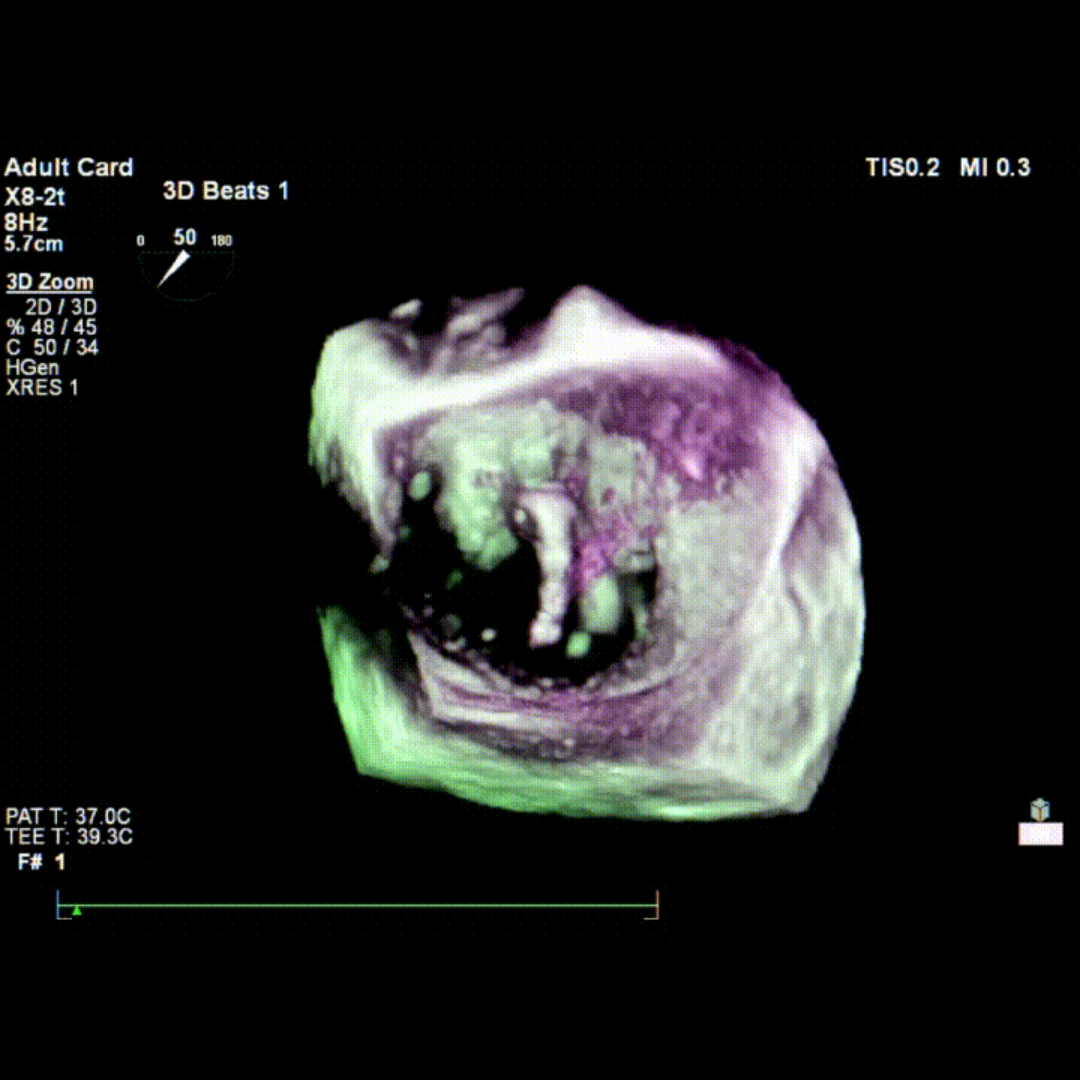

会议期间,张海波教授团队联合李伟教授完成了一例TA-TEER现场手术演示。患者为混合性二尖瓣反流(DMR+FMR),伴瓣环扩大、前瓣叶冗长、三区反流、后叶栓系及短小等复杂情况。术者在充分评估后选择置入双夹,手术获得圆满成功。现场专家就夹子型号选择、双夹放置位置及三区交界病变穿刺点等问题展开了深入讨论。

术中TEE影像